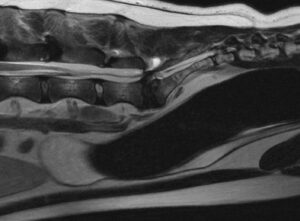

Holly, a 6-year-old German Shepherd, was brought in for evaluation due to pain and reluctance to use her left hind leg. Her discomfort became more pronounced after strenuous activities, such as jumping onto elevated surfaces. Upon examination, decreased muscle tone and strength were noted in her limb, along with atrophy in her gluteal and hamstring muscles. An MRI revealed that Holly was suffering from lumbosacral stenosis (LSS), a common condition in German Shepherds, comparable to sciatica in humans. The nerves affecting her back legs and tail were being compressed between the last lumbar vertebra and the sacrum (tailbone). The compression worsened when Holly bent backward, as in jumping, but improved in a flexed or fetal position.

The recommended treatment was surgery to relieve the pressure on the nerves and stabilize the moving segment in the more comfortable flexed position. Polyaxial screws and rods from the Arcas System by ArteMedics were used to align and fix the bones in the ideal position. Holly recovered quickly and was able to go home the day after surgery. We are thrilled with her new mobility and look forward to her long-term comfort.